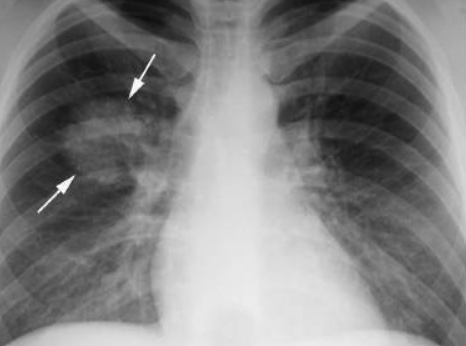

在進ICU的第二天,我的呼吸還不穩定,依靠8L的氧氣、抗生素和抗病毒藥物來擊退新冠病毒。醫生讓我趴著休息。因爲這樣可以讓肺張開。才會吸收多點氧氣。

但是,一到下午我開始出現呼吸困難。我用盡全力大口的呼吸,始終有種喘不上氣的感覺,那時我的血氧飽和度已下降到85%。

醫生就幫我的氧氣開到最大。醫生說:如果明天你的血氧飽和度還在下降的話,就非常危險了,需要插管,那時候需要你處于昏迷的狀態,從喉嚨插一個管,然後用呼吸機來幫助肺呼吸。

在進ICU的第三天,我的還是覺得呼吸困難,感覺喉嚨好像被堵住了,躺著呼吸都有些困難,雖然氧氣面罩一直戴著,但是就感到吸不到氧氣,醫生非常嚴肅的說,因爲你的肺部受到了病毒的感染,所以會一直覺得缺氧,下午2pm准備插管吧,在這之前,你可以跟你的家人視頻通個話。

醒來之後,我的情況慢慢好轉了,在進入ICU的第七天,我的血氧飽和度98%。醫生把我的氧氣降到5L,護士說我康複的很快,而在我隔壁房間的已經插管10天,到現在還沒醒,情況一直沒有好轉,可能撐不下去了。

離開ICU後,我又在住院部住了8天,做了CT,肺部損傷30%,在ICU的這8天,我真的感覺像是在鬼門關附近走了一圈,差一點就一只腳就邁進去了,我在醫院裏如此努力地與新冠病毒作鬥爭是有原因的,因爲我一生從未戰勝過任何事情。現在,作爲一個COVID幸存者,我贏得了只要活著就會永遠珍惜的東西——我的生命。